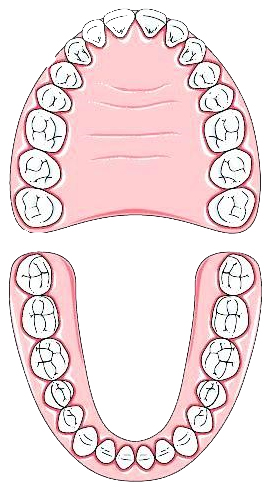

Жевательный отдел в норме составляют 5 зубов, расположенных после клыка на нижней и верхней челюсти, справа и слева: два премоляра (малые жевательные зубы), три моляра (большие жевательные зубы). Последние моляры, они же зубы мудрости, требуют особого подхода в лечении, подробнее об этом можно прочитать в этой статье.

Жевательный отдел в норме составляют 5 зубов, расположенных после клыка на нижней и верхней челюсти, справа и слева: два премоляра (малые жевательные зубы), три моляра (большие жевательные зубы). Последние моляры, они же зубы мудрости, требуют особого подхода в лечении, подробнее об этом можно прочитать в этой статье.